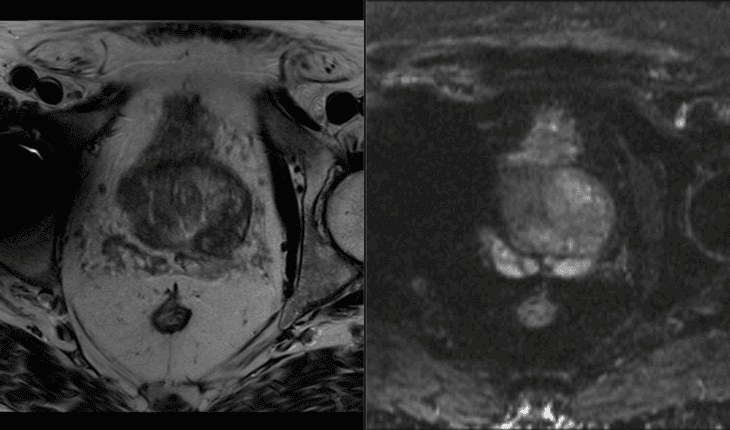

AI-QUAL leverages advanced artificial intelligence to evaluate prostate MRI studies and assign a standardized score from 1 to 3, reflecting the diagnostic quality of the images. The system automatically detects common artifacts—such as rectal gas distortion and metal interference—that can compromise image quality and reduce diagnostic accuracy.

Recent studies have shown that one in three prostate MRI scans in the US are not of diagnostic quality, underscoring the urgent need for automated, objective quality control tools in prostate imaging.

Low-quality imaging has been linked to an increase in PI-RADS 3 findings, which can lead to unnecessary biopsies and negatively impact patient care. AI-QUAL addresses this challenge by providing a standardized, automated approach to image quality assessment, helping clinicians make more confident and informed decisions.